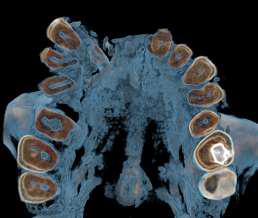

FIGURA 1 (TOMOGRAFIA VISTA FRONTAL)

RECONSTRUCCION 3D DE LA ZONA A ESTUDIAR

Las reconstrucciones tridimensionales nos permiten una visualización detallada y precisa de las estructuras vecinas a la pieza retenida, superando las limitaciones 2D de las radiografías convencionales, también ayudara en este caso para la planificación quirúrgica y posterior tratamiento de ortodoncia.

En este caso podemos observar una lesión de diámetro considerable de bordes corticalizados y forma irregular proyectada en el maxilar superior en el cuadrante 1, que se extiende desde distal de la pieza 1.1 hasta distal de la pieza 1.5, desde el tercio apical de las piezas 1.2 – 1.4 y 1.4 por vestibular y desde cervical por palatino. Se evidencia también a la pieza 1.3 retenida desplazada el ápice hacia la cortical palatina y la corona hacia la cortical palatina

CORTES AXIALES

Con la evaluación de la tomografía volumétrica en cortes axiales y transversales se observa la expansión y adelgazamiento de la tabla ósea vestibular y palatina legando a dicha pérdida ósea, también se observa el desplazamiento de la pieza 1 3 la cual se encuentra retenida y desplazada hacia la basal vestibular.

CONCLUSION

CORTES SAGITALES

A nivel de los cortes sagitales y coronal verificamos la extensión de la lesión y evidenciar el desplazamiento de las piezas 1.2 a mesial y 1.4 hacia distal a causa de la retención de la pieza 1.3 y expansión de la lesión